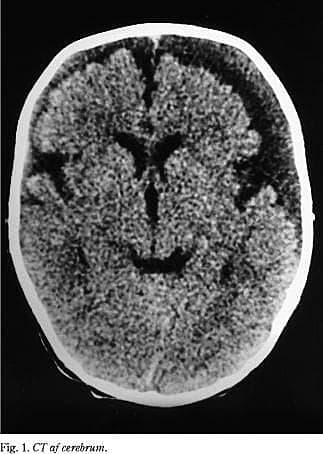

Barnet blev indlagt til videre udredning, og en CT af cerebrum viste bilateral frontoparietale ansamlinger i form af hygrom, kombineret med subdural blødning, samt diskrete tegn på pågående blødning (Fig. 1 ). Øjenundersøgelse samt helkropsrøntgen viste retinale blødninger samt proksimal radius fraktur med udtalt callusdannelse.